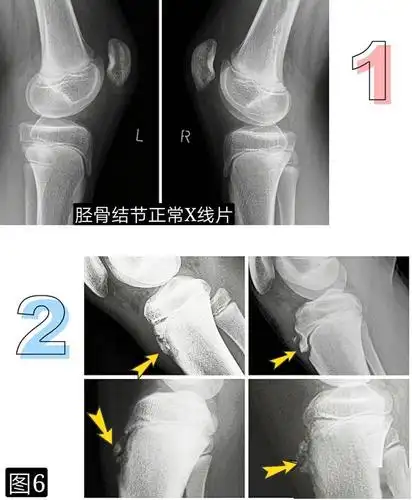

胫骨结节骨软骨炎

胫骨结节骨软骨炎_软骨炎_发病原因_症状表现_治疗方式 - 好大夫在线

胫骨结节骨软骨炎影像表现与鉴别诊断